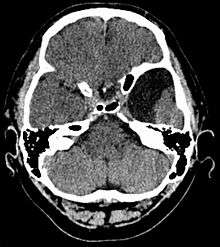

Arachnoid cyst